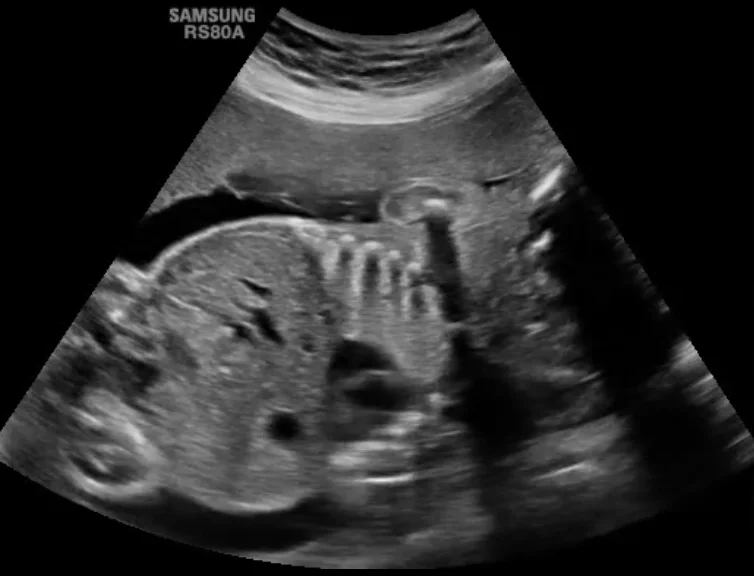

Thoát vị hoành bẩm sinh thai nhi (Congenital Diaphragmatic Hernia)

• Thoát vị hoành bẩm sinh thai nhi (Congenital Diaphragmatic Hernia)